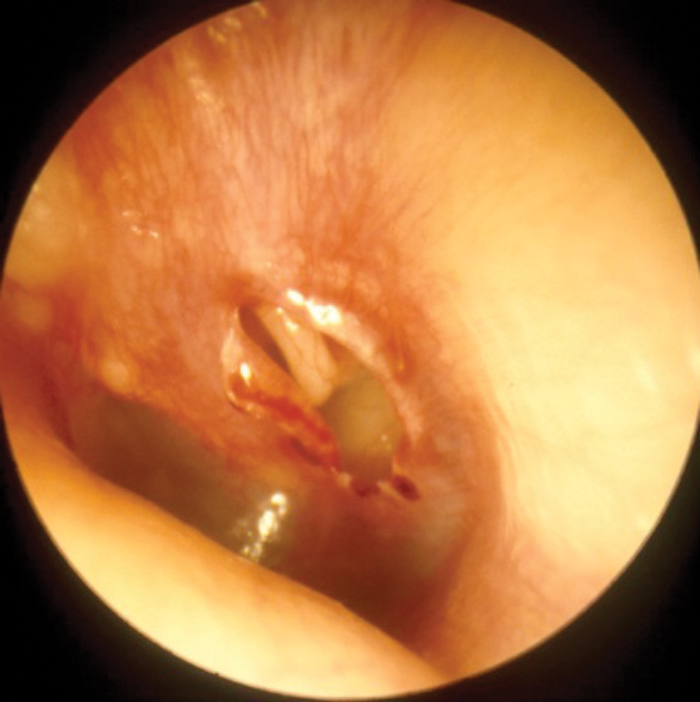

Middle ear barotrauma may be avoided by the simple solution of inserting ventilation tubes. Whilst this does not give rise to difficulty in aviators, they are contraindicated in divers because of the risk of water passing into the middle ear cavity. As already mentioned, divers may avoid middle ear barotrauma by aborting the dive, and if this is a persistent problem, the individual will be made unfit to dive. Occasionally, even an experienced diver will be required to dive rapidly, perhaps to go to the rescue of a buddy in difficulty, and this may lead to middle ear barotrauma. Grading systems exist, but the author favours a description of, ‘mild’, ‘moderate’, and ‘severe’. Initially there is hyperaemia of the tympanic membrane; followed by a middle ear effusion which may contain blood; and then perforation of the tympanic membrane. If the barotrauma has been relatively rapid, there may be little more to see than a perforation, which tends to be a tear in the tympanic membrane, rather than a hole - Figure 2.

Figure 2: Traumatic perforation.